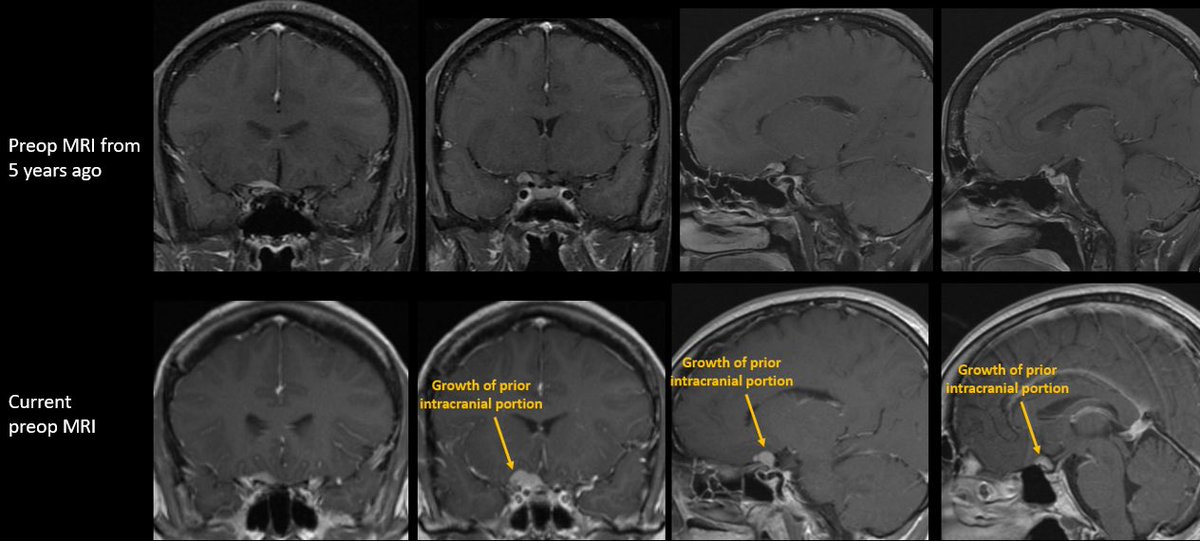

How would you manage this 42F w/ intracranial recurrence of optic nerve sheath meningioma initially biopsied at OSH 5 yrs ago. R eye blind, L 20/20, EOMI. Observation? Radiation? If surgery, approach/extent of resection? #Neurosurgery #MedEd #MedTwitter @EvaWuMD @TheJNS @WFNSHQ